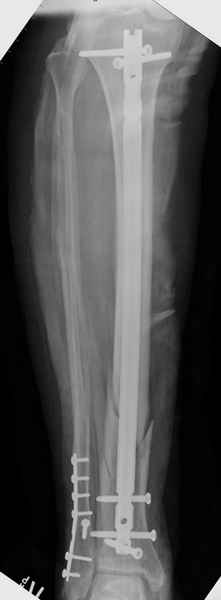

Повреждение такой локализации, на которой применимы и аппарат (классический Илизарова или гибридный), пластина, особенно Locked Plate, и гвоздь с блокированием. В нашей клинике был бы выполнен закрытый интрамедуллярный остеосинтез. Желательно использовать гвоздь с возможностью провести более чем 2 обычных фронтальных винта в дистальном отломке.

Здесь мы использовали новый Synthes Nail с дополнительными дырками, в проксимальной части 4: по две косых и поперечные (один стандартный а другой динамический), в дистальной части две поперечные, прямая и косая. Вес больного более 120 кг, нагрузку начнем через месяц.

Получилось красиво, поздравляю. Вверху можно было ограничиться одним винтом во фронтальное статическое отверстие, зачем два 45-градусных?

При такий спирали задний край tibia может быть сломан - нет ли этого в данном случае? На всякий случай можно было ввести 1-2 винта 4,5 мм спереди назад мимо гвоздя. Хотя самый дистальный блокирующий винт, возможно, зацепил этот отломок. А какой тут диаметр гвоздя и locking винтов?